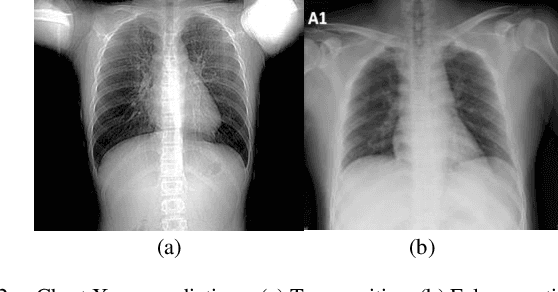

Abstract:Spreading of COVID-19 virus has increased the efforts to provide testing kits. Not only the preparation of these kits had been hard, rare, and expensive but also using them is another issue. Results have shown that these kits take some crucial time to recognize the virus, in addition to the fact that they encounter with 30% loss. In this paper, we have studied the usage of x-ray pictures which are ubiquitous, for the classification of COVID-19 chest Xray images, by the existing convolutional neural networks (CNNs). We intend to train chest x-rays of infected and not infected ones with different CNNs architectures including VGG19, Densnet-121, and Xception. Training these architectures resulted in different accuracies which were much faster and more precise than usual ways of testing.